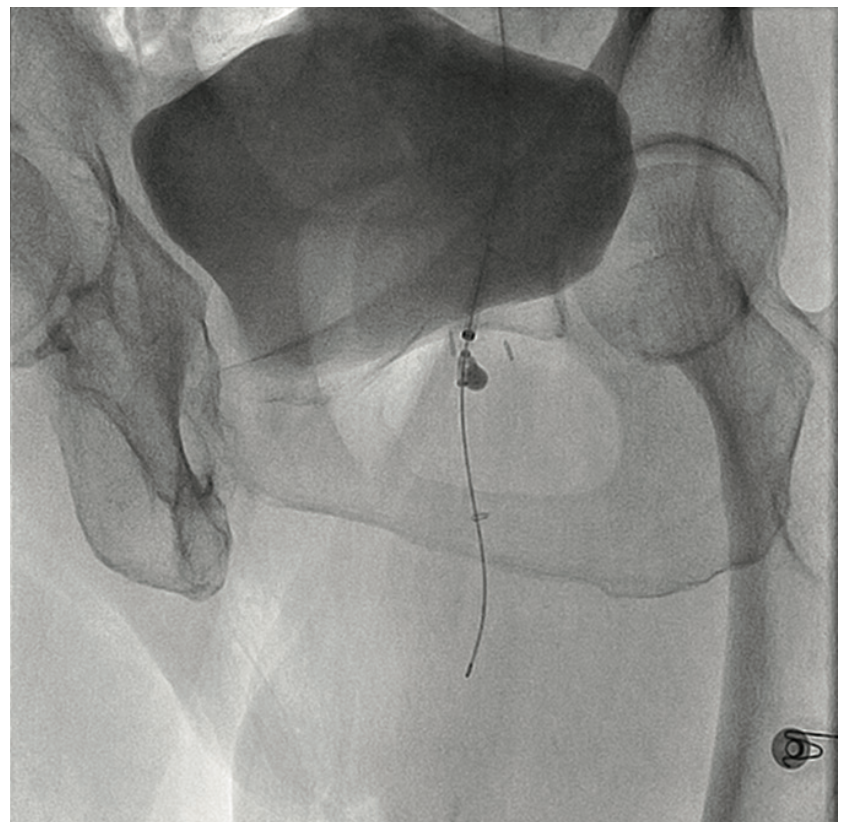

A 90-year-old woman presented with CLI of her left foot. She suffered from claudication beginning 12 years ago. Six months prior, she developed an ulcer on her foot and shortly thereafter, underwent femoral popliteal bypass. Her symptoms recurred and repeat fem-pop surgery was performed at that time. It immediately failed and she had a cadaveric vein placed as a fem-pop conduit, which again occluded and after two revisions of the fem-pop bypass, she was told five months prior to her current presentation that she would not be able to have any further intervention on her leg. At that time, it was suggested she go to hospice. A medial 1 cm x 6 cm foot ulcer was noted on examination, but the patient refused any intervention. Six weeks later, with insistence from the wound care center, and with the patient’s second and third digit now black on that foot, the patient permitted an evaluation for possible limb salvage. The examination showed that the foot was now cool and the second, third, and fourth digits were bluish-black. No pedal pulses were present. The patient was approached via the contralateral groin, and the angiogram revealed her native SFA and graft to be occluded at the origin (Figure 8). With the thought that there was a likelihood of thrombus in the vessel, we utilized the CrossLock LP and crossed the occlusion down to the tibial vessels with a Command wire (Abbott Vascular) wire (Figures 9-10). With some suggestion of thrombus in the digital arteries, 3 mg of tPA was administered locally. A .9 laser was used and subsequent balloon angioplasty was performed using embolic protection (Figures 11-12). The fluoroscopic time was 25.2 minutes and contrast was 273 cc. At the end of the procedure, the patient had 2-vessel infrapopliteal flow and several hours later, was seen by the orthopedic surgeon for metatarsal surgery. The surgeon stated that all the toes were now pink, the patient had palpable pedal pulses, and although it was very likely that some amount of amputation may be necessary in the second and third toe, nothing was removed, and the patient was discharged the next day.